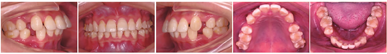

曲面断层片示28、38、48阻生;牙根发育良好,双侧髁突形态结构对称,骨皮质连续;牙槽骨及下颌骨未见明显异常(图2)。CBCT显示:上下前牙牙根靠近唇侧骨皮质,下前牙区骨皮质较薄(图2)。

头颅定位侧位片及头影测量结果示:ANB角与Wits值表明患者为Ⅰ类骨面型;FMA提示患者为低角;U1-NA角、L1-NB角及U1-L1角均表明上下切牙唇倾(表1)。